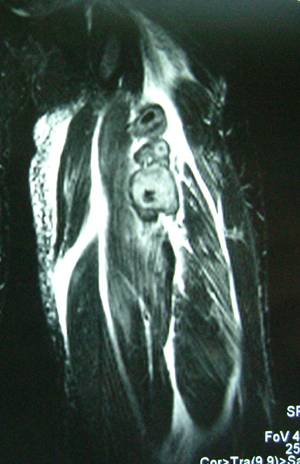

大腿ハムストリング腱断裂MRI画像

大腿ハムストリング腱断裂 術後4週間

大腿ハムストリング腱断裂 術後4ヶ月